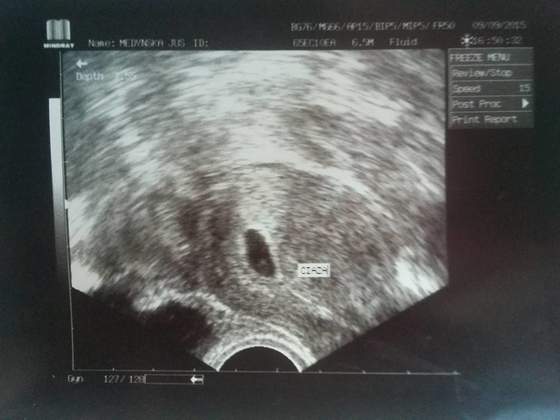

Ja dzisiaj po wizycie - zarodek 3.5mm serduszko bije <3 to najważniejsze

Wsumie nic więcej sie nie dowiedziałam, kolejna wizyta 12.10, nie wyliczył mi spodziewanej daty porodu wiec może na kolejnej wizycie sie dowiem

Karta ciązy założona